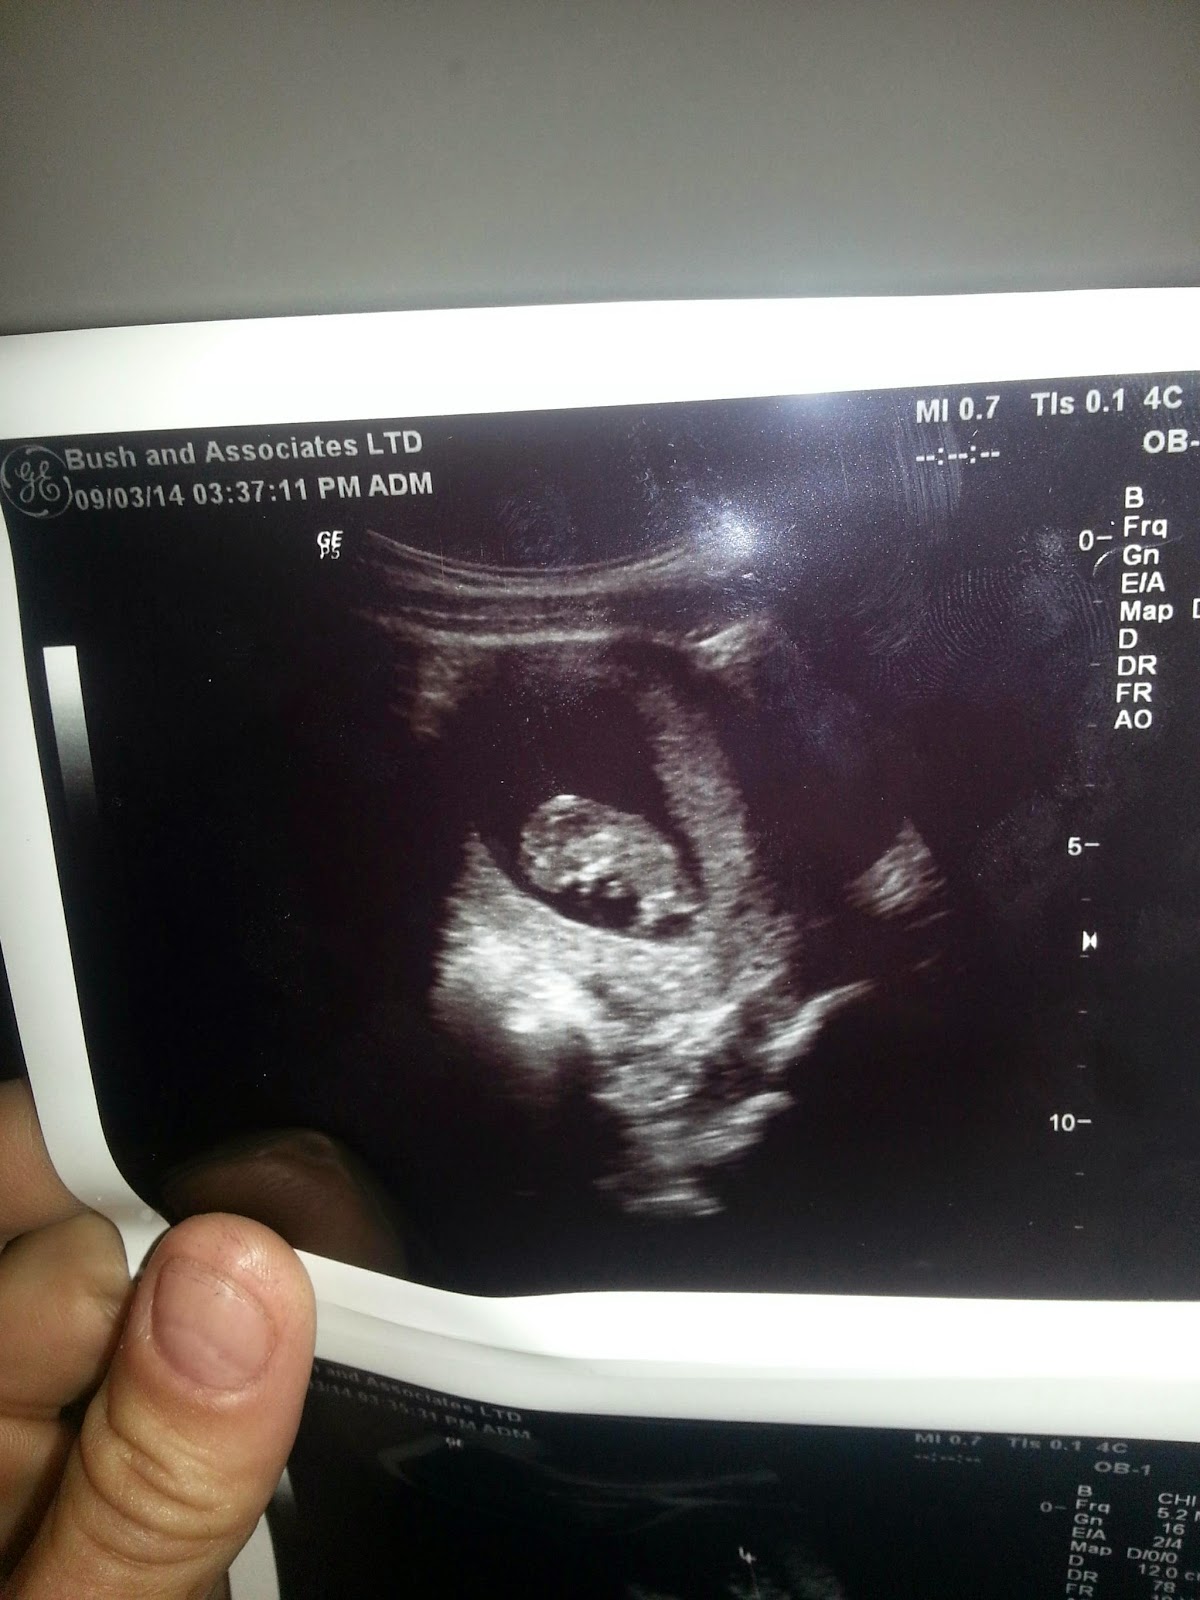

So, my cycles have been all over the place in the 6 months since my last m/c. . . anyone else experience this? Anyways, it made it hard to estimate how far along I was but i was guessing about 6 weeks based on my symptoms, PGAL brain was causing me to hope for 8 wks but that seemed impossible. We went to the first prenatal appt. yesterday and the u/s showed 10 freakin' weeks of development! I've never made it past 8 wks before so of course I laugh/cried so hard she lost the image. I've never had good u/s experience before and I was really starting to doubt that I could ever make it even this far. Hope this encourages other first tri ladies to hang in there!

Re: first u/s surprise (pic warning)